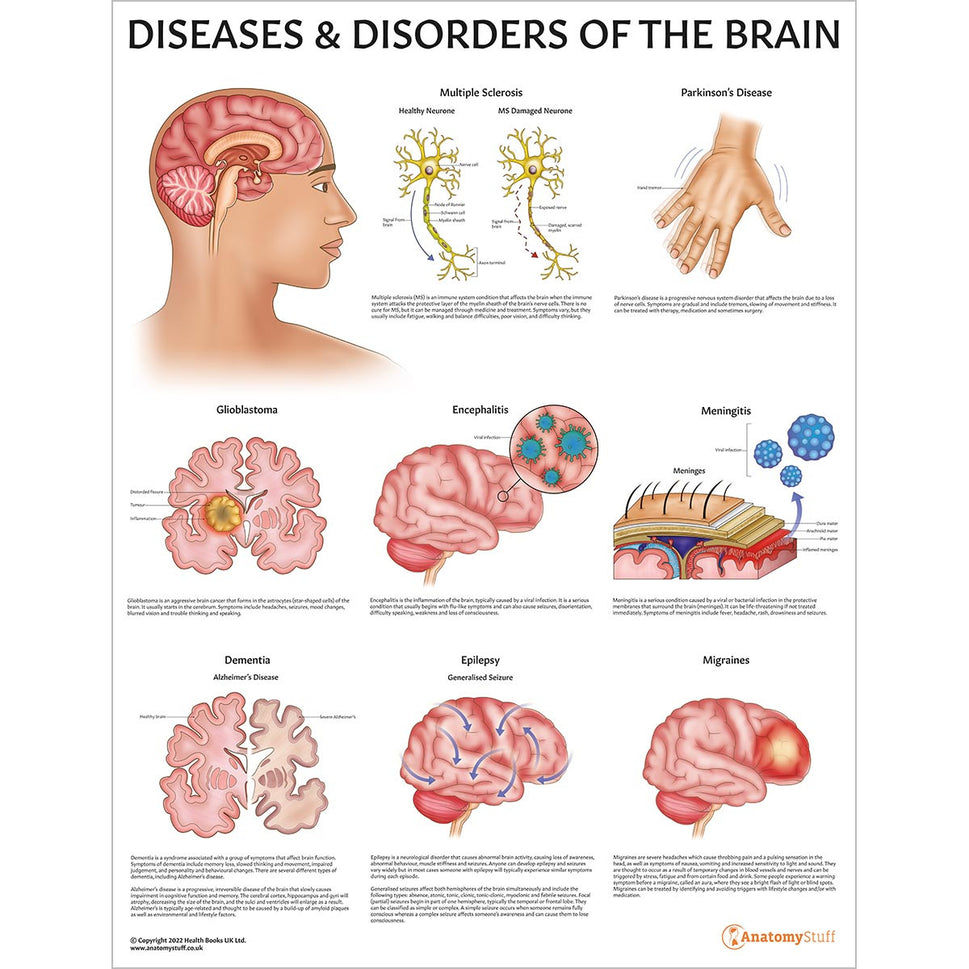

Enhance medical education with our collection of digestive system anatomical models including the stomach, liver, gallbladder, pancreas & colon models. Discover the anatomy of healthy organs as well as common gastrointestinal diseases such as stomach ulcers, gallstones and liver cirrhosis. Our digestive system anatomy posters are ideal for study and patient education.

At AnatomyStuff we stock a diverse range of digestive system anatomical models to suit your training needs. From budget models and affordable medical education posters to highly advanced 3D printed bowel models, you can transform medical training and patient education. As well as our own exclusive collection, we are proud resellers of 3B Scientific, Anatomy Lab, Denoyer-Geppert Science Company, ESP Models, Erler Zimmer and GPI Anatomicals. Explore our exclusive collection of digestive system anatomy charts, posters, fine art prints and digital anatomy study guides. Discover the anatomy of key organs like the liver, stomach, pancreas and bowel as well as the pathophysiology of common conditions like peptic ulcer disease, coeliac disease, IBD and much more. We have anatomy posters suitable for school children all the way up to medical degree level. From a liver anatomy poster to a digital study guide all about common GI disorders, find exactly what you need right here to enhance medical training and patient education.